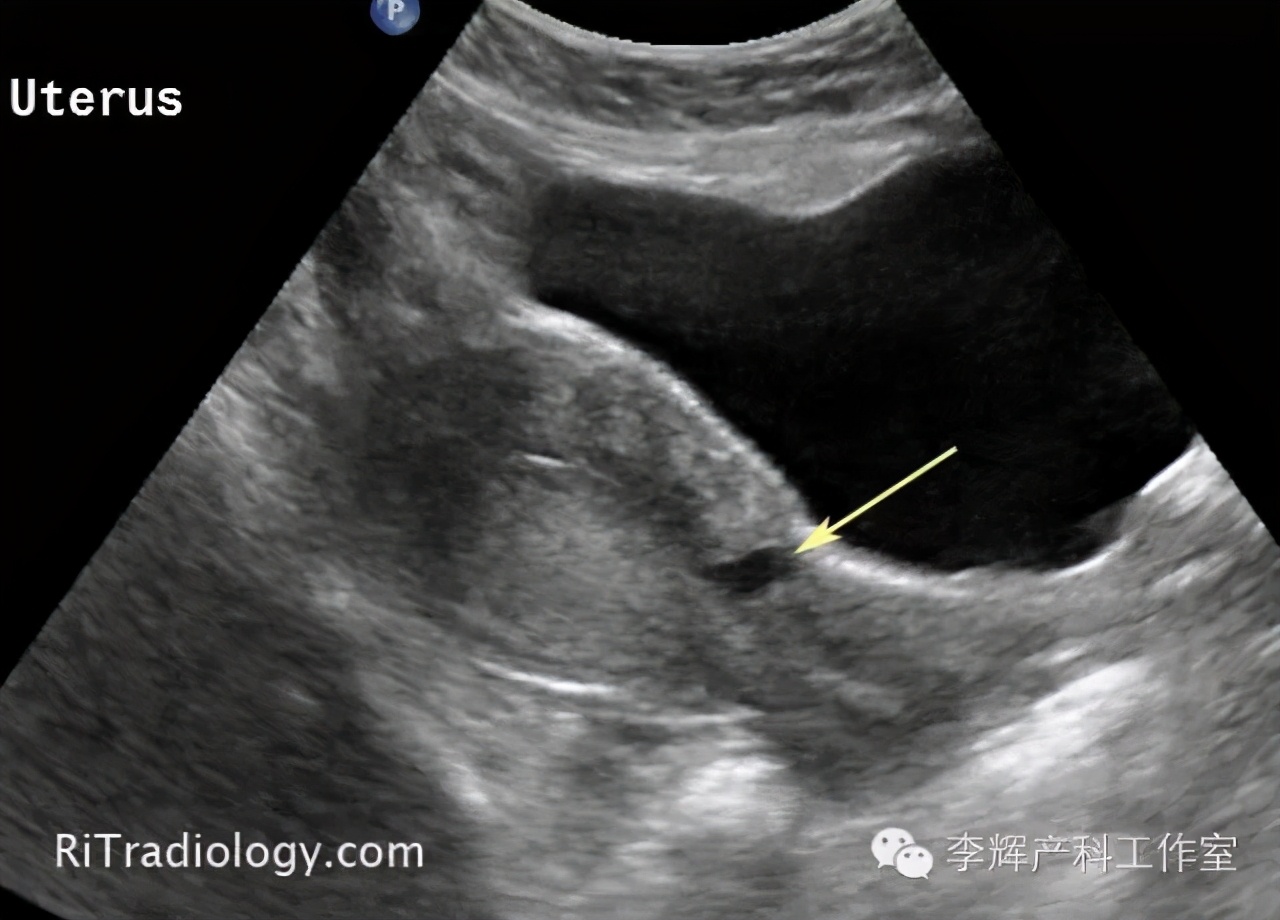

10.术后腹壁切口愈合不良可能,产妇发生率不高,多发生于产程中剖宫产、胎膜早破,糖尿病,重度贫血产妇。发生了切口愈合不良,不是因为没有缝合好,绝对跟产妇体质有关。也有的产妇发生子宫切口愈合不良,形成憩室,术后表现为淋漓出血,必要时需要再次手术修补。